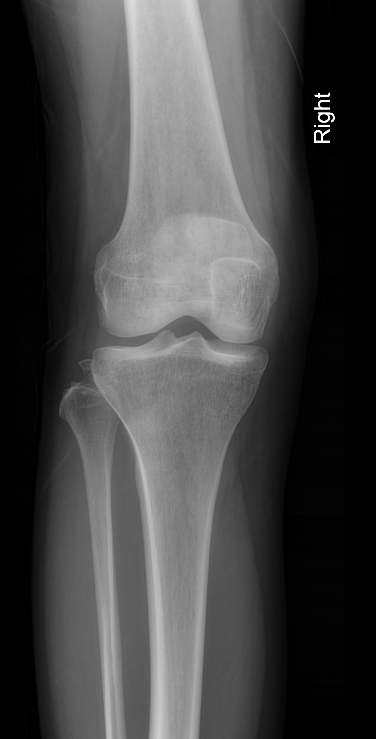

VERY HIGH A/W ACL

The arcuate sign is often a subtle but important finding on knee x-rays and represents an avulsion fracture of the proximal fibula at the site of insertion of the arcuate ligament complex, and is usually associated with cruciate ligament injury (~90% of cases) 2. The fracture fragment is attached to the lateral (fibular) collateral ligament, the biceps femoris tendon, or both.